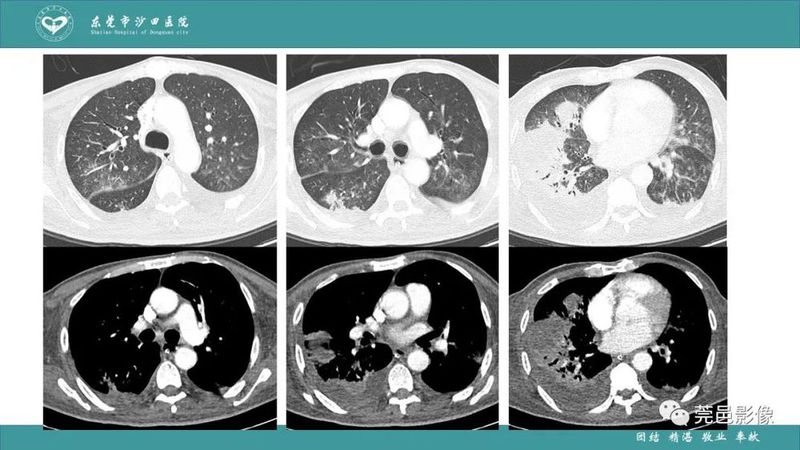

「肺炎克雷伯杆菌肺炎」影像学诊断+鉴别诊断